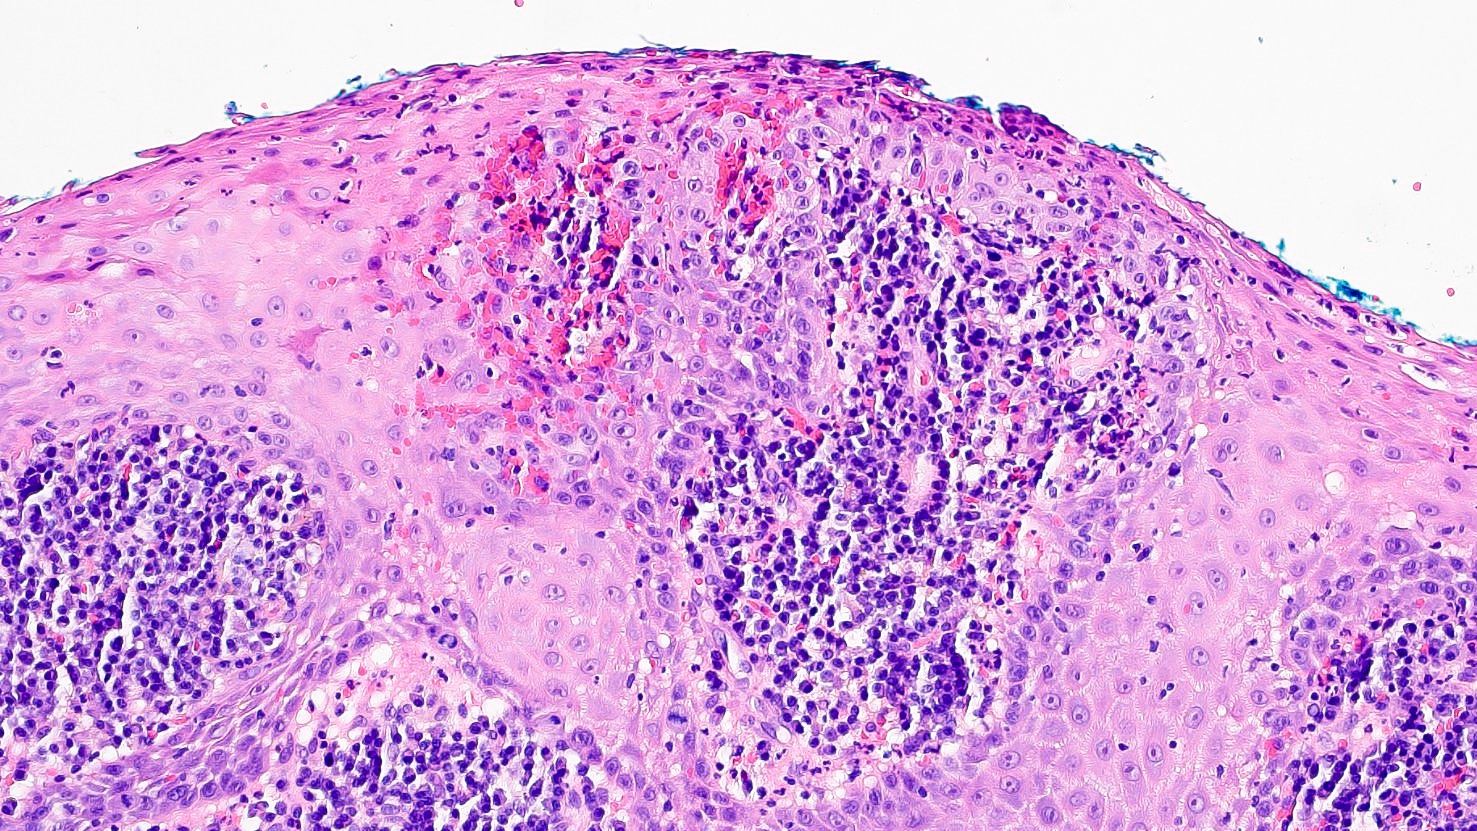

Microscopic (histologic) description

• Thick elongation of the overlying epithelium with bulbous or sometimes jagged / sharp, interconnecting rete ridges (Am J Dermatopathol 2011;33:112)

• May exhibit keratin pearl formation: concentric layers of keratinocytes with central keratinization (Am J Dermatopathol 2011;33:112)

• Lacks significant nuclear atypia; although mitotic figures may be seen, they are not numerous or atypical (Am J Dermatopathol 2011;33:112)

• Prominent leukocytic exocytosis or extravasated red blood cells should alert the pathologist to look for infection (candidiasis, blastomycosis, etc.) or granulomatosis with polyangiitis (Am J Dermatopathol 2011;33:112)

Practice question #2

A patient presents with a yellow nodule on the tongue. What is the diagnosis?

1. Frictional keratosis

2. Granular cell tumor with overlying pseudoepitheliomatous hyperplasia

3. Squamous cell carcinoma

4. Verrucous carcinoma

Practice answer #2

B. Granular cell tumor with overlying pseudoepitheliomatous hyperplasia (PEH). Microscopic sections show a dome shaped mass of pale, basophilic, plump granular cells surfaced by hyperkeratotic and hyperplastic epithelium. Although the rete ridges are significantly proliferative and demonstrate keratin pearls, overt cytologic atypia is not appreciated. This proliferative pattern of the epithelium is termed pseudoepitheliomatous hyperplasia and is known to be associated with granular cell tumors. Answer A is incorrect because although there is a thickened layer of parakeratin, this answer choice ignores the replacement of the fibrous stroma by plump granular cells. Answer C, a common pitfall in the diagnosis of this tumor, is incorrect because although the epithelium is proliferative, prominent cytologic atypia is not appreciated. The pathologist must be keen in recognizing the underlying replacement of the fibrous stroma with plump granular cells and must know that granular cell tumors characteristically show PEH in many cases. Answer D is incorrect because verrucous carcinoma would show keratin clefting and prominent, bulbous, plunging rete ridges that push into the underlying muscle.